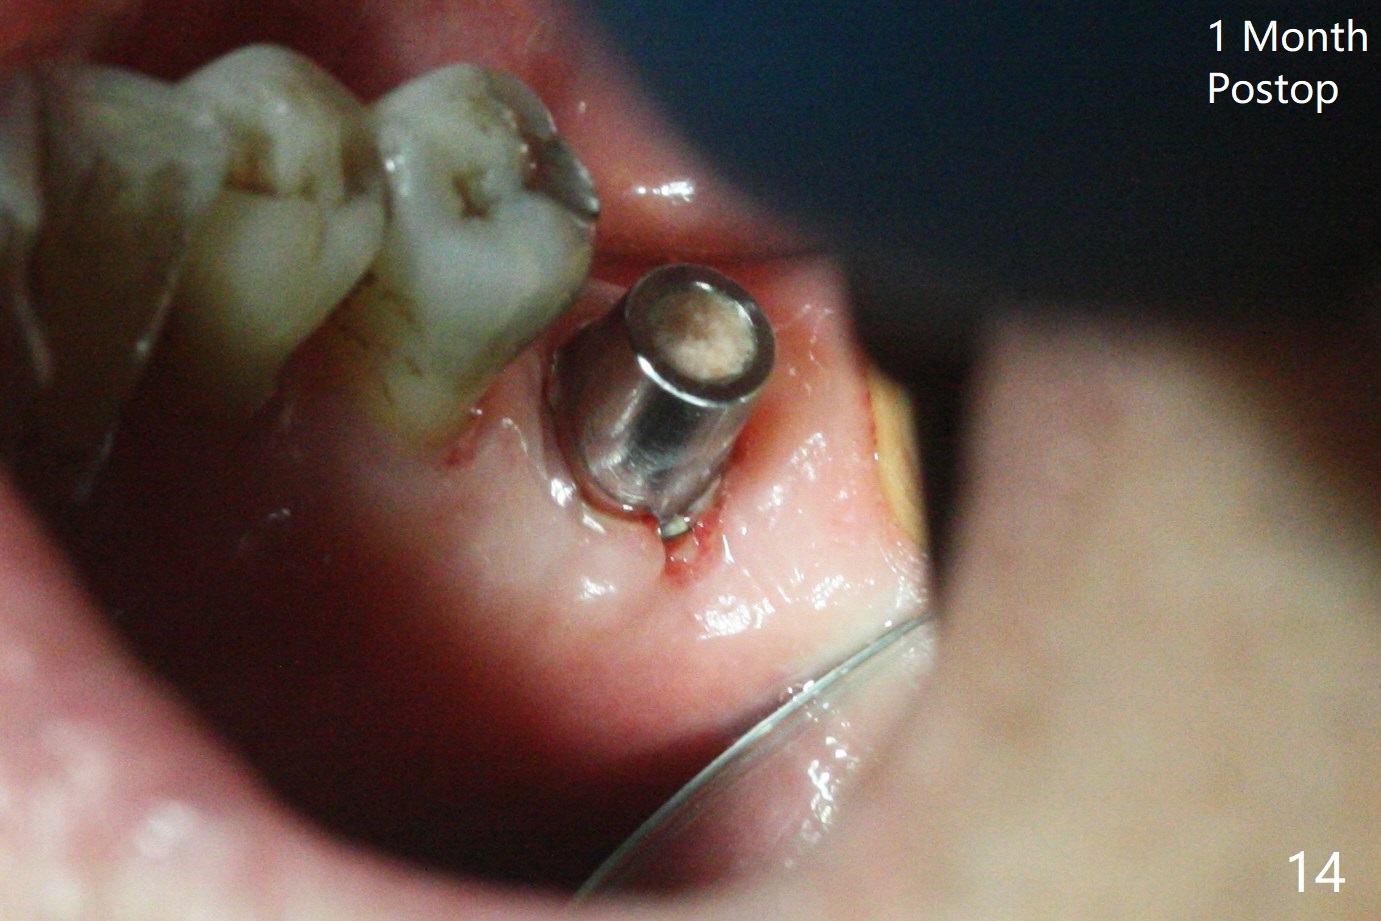

As planned, the crown of the tooth #30 with lingual (Fig.1 L) caries is removed and flattened with surgical handpiece so that the guide is able to be seated without interference. The osteotomy by 10.5 mm offset bone trimmer is lingual (Fig.2 white circle; due to in part the lingual caries and in part design error); in order to let the osteotomy to bounce back buccal, the part of the buccal roots are removed by surgical bur (arrows). The initial osteotomy by 2.2 mm drill is in the middle of the septum (Fig.3). After the last drill (3.5x11.5), the remaining roots are easily removed with proximators; a 4x11 mm dummy implant is placed with low stability and supracrestal lingual (Fig.4). Therefore a 4.5x9 mm final implant is placed with low torque. Following 4x11.5 mm drill, the torque increases to 20 Ncm. With insertion of healing screw, sticky bone (Fig.4 *: .5-1 mm cortical/cancellous allograft) is heavily packed around the implant (arrow), which apparently allows removal of the healing screw and placement of a 6x5.7(3) mm pair abutment without loosening the underlying implant. More bone graft is placed (Fig.6), followed by 2 pieces of PRF membranes. Although the implant is slightly buccally placed (Fig.7, due to over-removal of the buccal root, Fig.2 arrows), it is placed in the septum (Fig.8 S). To further compensate for the low implant stability, setting acrylic is applied in the edentulous area, particularly into the undercuts of the neighboring teeth (Fig.9 *) and around the abutment. The lingual margin of the acrylic dressing is extended (Fig.10 arrow) to cover the soft tissue defect associated with the lingual caries. As compared to the design (4x10 mm, Fig.11), the implant (4.5x9 mm, Fig.12) is placed buccal and ~ 2 mm deeper, reducing the chance of periimplantitis. The acrylic dressing is in place, but has mobility. The gingiva is healthy 2 weeks postop. The dressing is removed 1 month postop; the socket heals around the abutment buccal (Fig.13) and lingual (Fig.14). In spite of the immediate provisional, the abutment margin is substantially subgingival mesial 4 months postop, extremely difficult to take impression. A smaller diameter and longer cuff abutment is placed (Fig.15). The lingual gingiva heals normal 5 months postop, immediately before cementation (Fig.16).